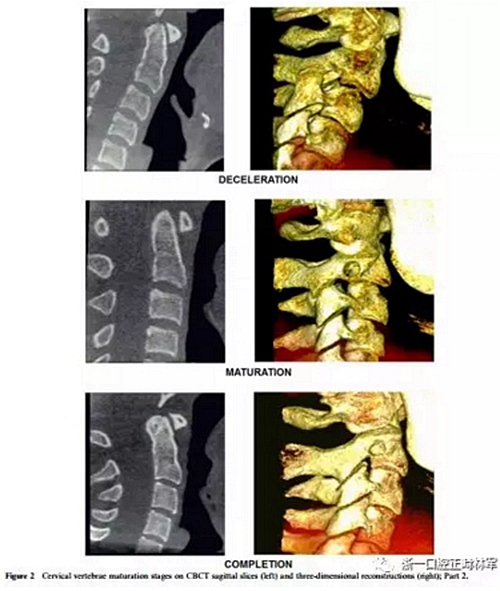

將CBCT三維重建和矢狀切片隨機(jī)分組,并使用軟件OsiriX®(The Osirix Foundation,Geneva,Switzerland)評(píng)估兩次。這些圖像在MacBook Pro(Apple Computer Inc.,Cupertino, CA)。使用OsiriX軟件,通過使用三維成像技術(shù),從醫(yī)學(xué)文件中的數(shù)字成像和通信獲得三維圖像重建。通過多平面重組獲得的矢狀切面是通過將光標(biāo)定位在沿中腭縫線和前鼻棘中心的線上來選擇的。為了避免視疲勞,每天只評(píng)估20幅圖像。評(píng)估分階段進(jìn)行,每次選擇一種展覽模式,第一次和第二次。CBCT圖像在昏暗的房間里,在具有亮度和對(duì)比度恒定特征的屏幕上進(jìn)行解讀,允許利用軟件的縮放,亮度和對(duì)比度工具來增強(qiáng)診斷。每個(gè)展覽模式的圖像解讀最短時(shí)間為15天。在第一次評(píng)估后1個(gè)月,考慮到3D重建和矢狀切片(圖1和圖2),讀片員再次讀片,獲取72條記錄。

4、減速期(頸椎成熟指數(shù)-4)

預(yù)計(jì)增長10-25%。椎骨C2,C3和C4的下部邊界呈現(xiàn)明顯的凹陷,并且椎骨C3和C4的體部呈現(xiàn)近似正方形的形狀。

5、成熟期(頸椎成熟指數(shù)-5)

這對(duì)應(yīng)于椎骨成熟的最后階段,預(yù)計(jì)5-10%的增長。在椎骨C2,C3和C4上觀察到更明顯的凹陷。后者有方形的體部。

6、定型(頸椎成熟指數(shù)-6)

現(xiàn)階段增長已經(jīng)完成。椎骨C3和C4的體部具有比水平尺寸和下邊界更大的垂直,下邊界保持明確的凹陷。